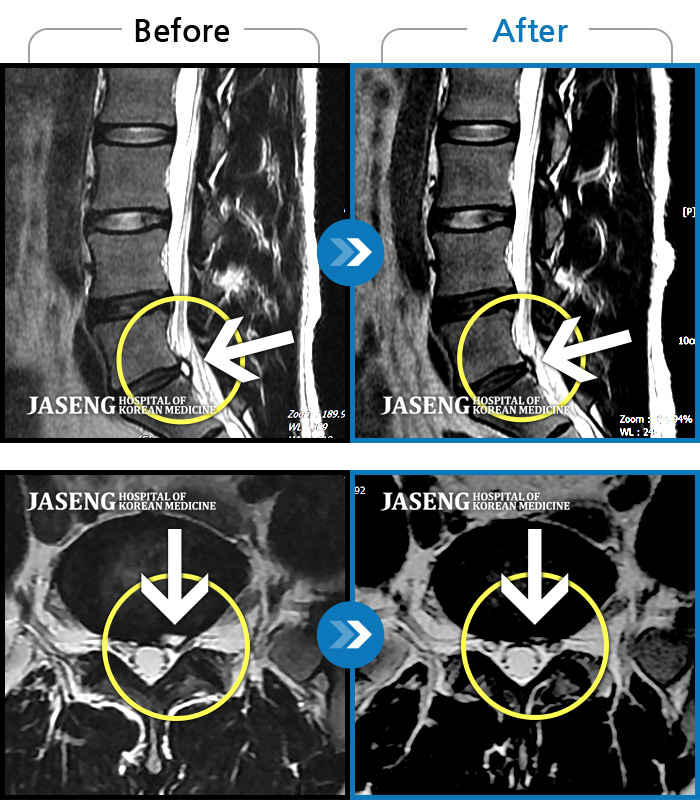

MRI ũ ʸ Ȯϼ.